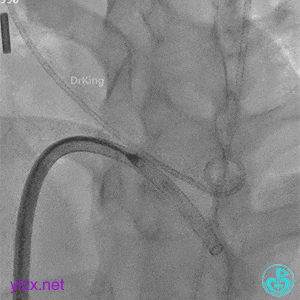

锁定封堵器后观察位置形态

锁定后可见位置形态完好,盘面平整,扣合良好,无周围瓣膜影响。